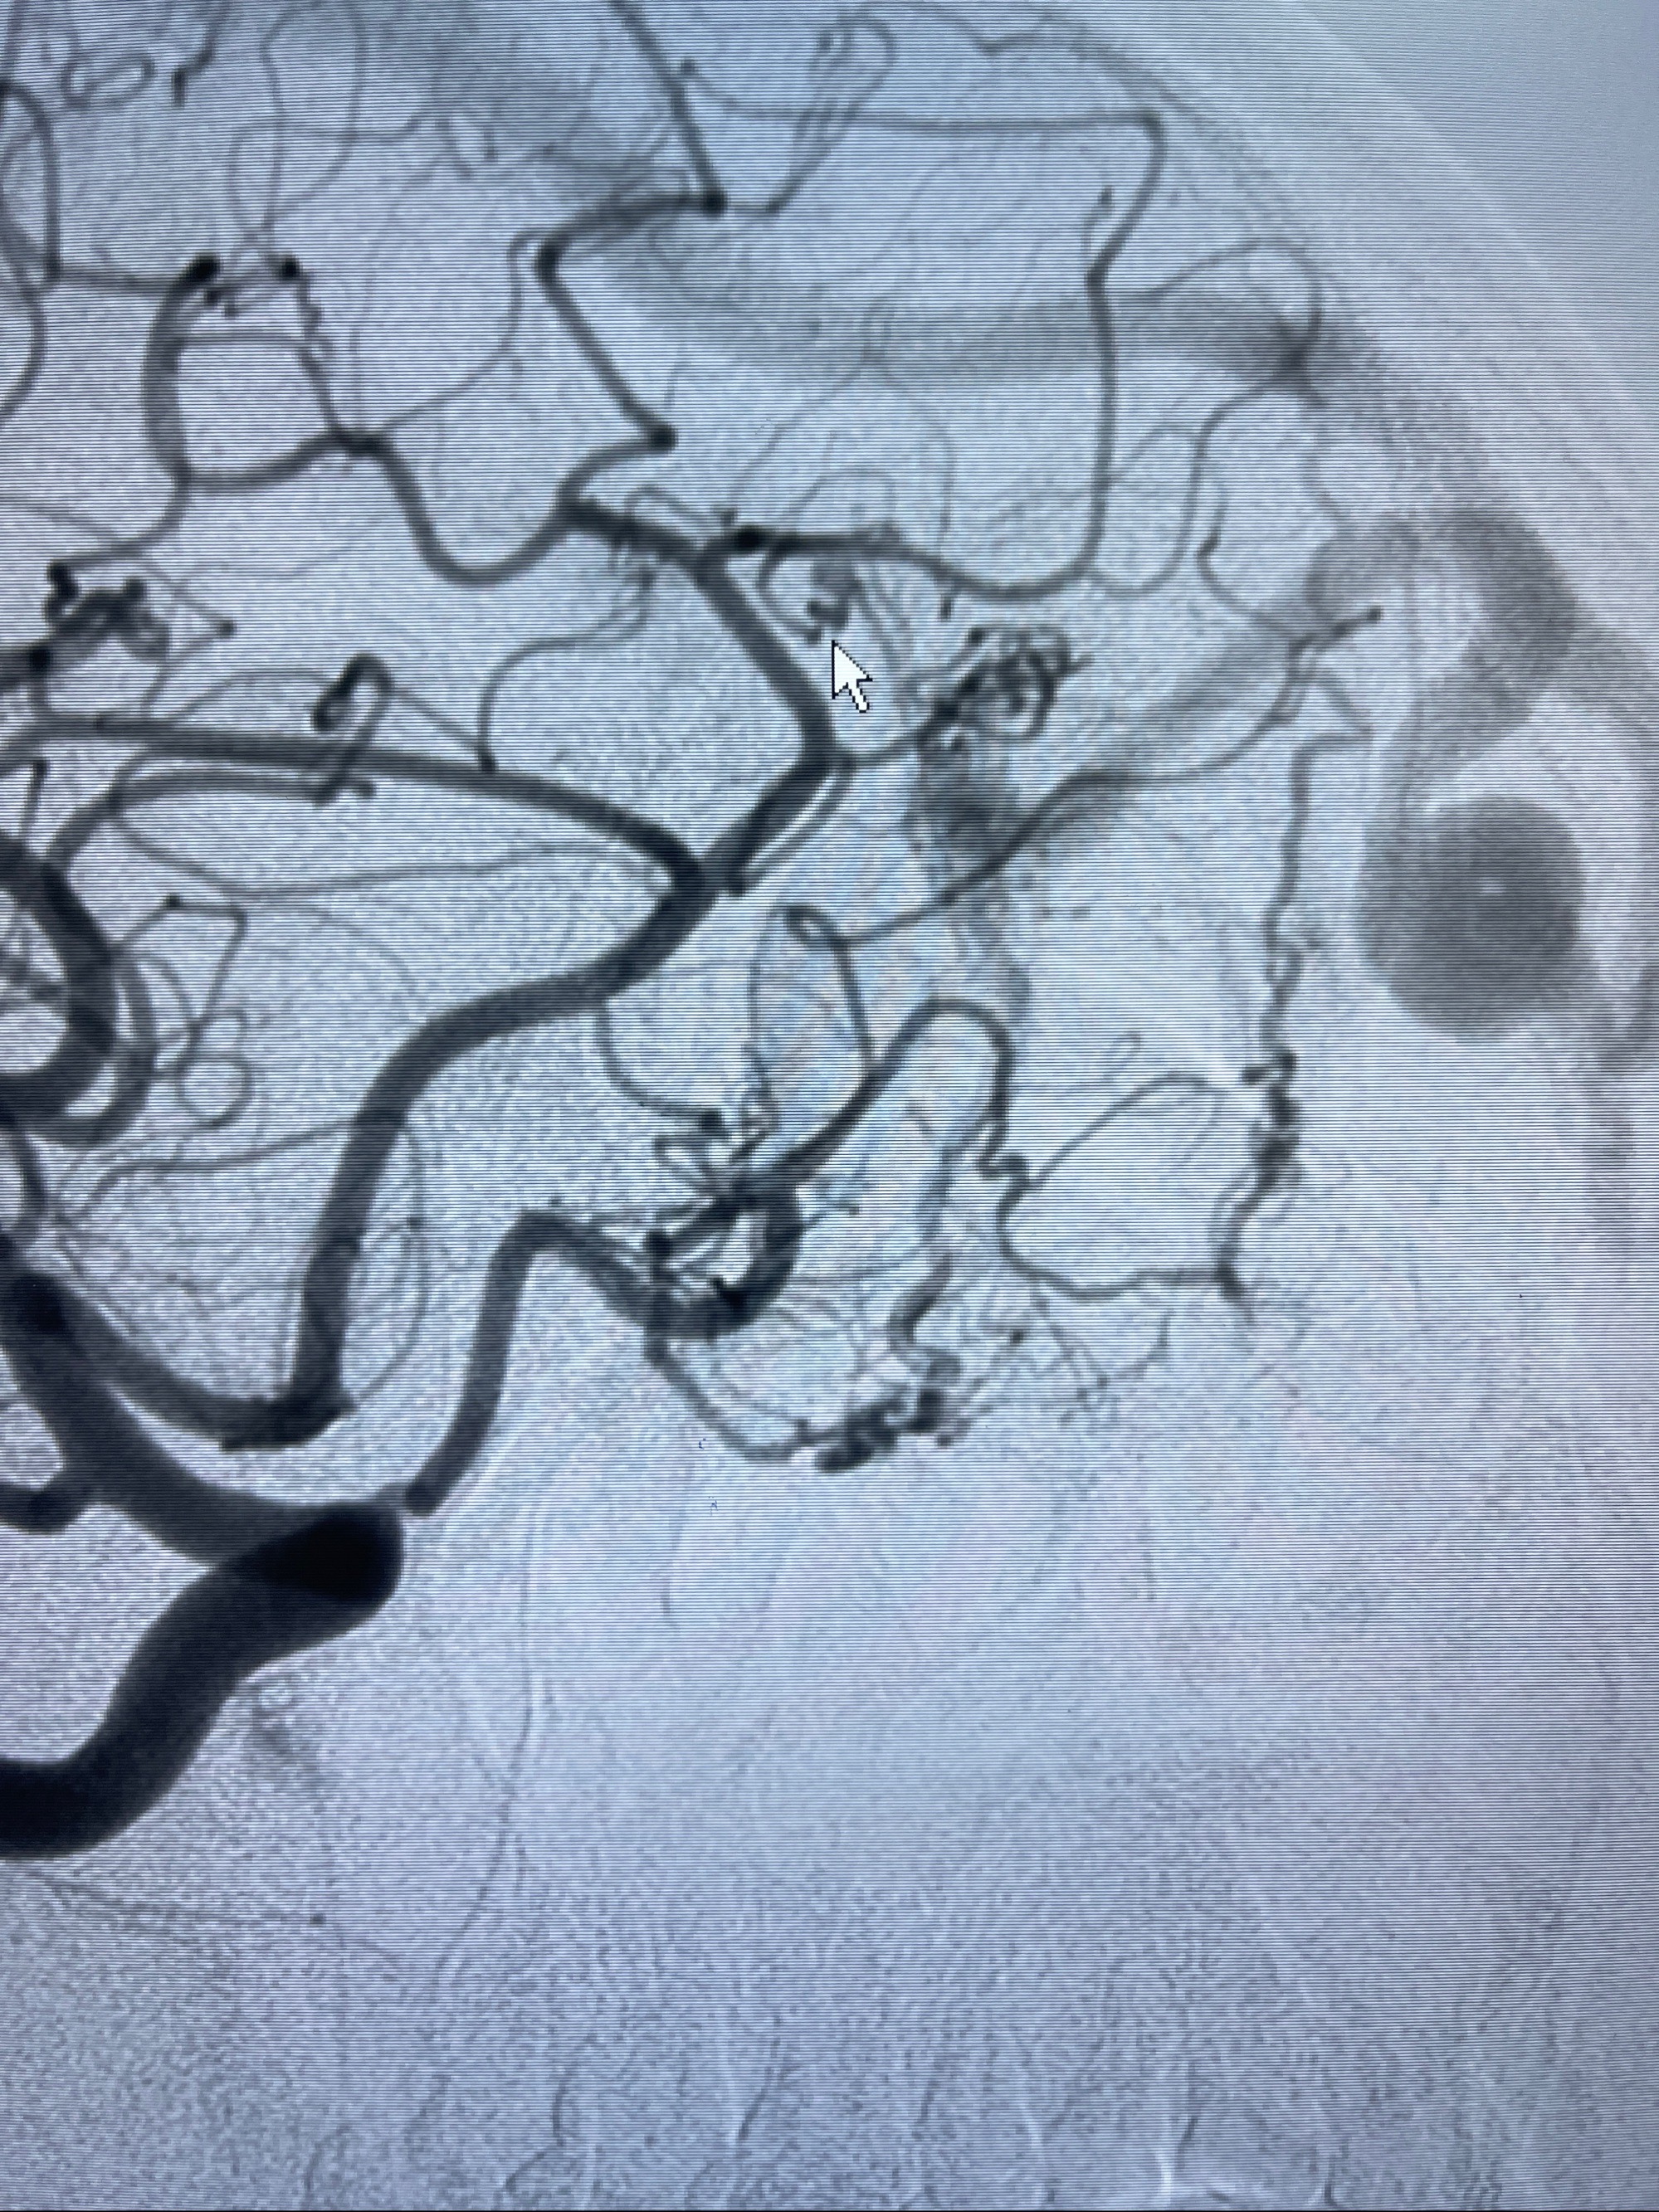

2023年8月21日]景德镇市第一人民医院脑血管造影检查,提示:主动脉弓、双侧颈总动脉、锁骨下动脉造影未见异常,左侧大脑前动脉静脉瘘。

2023-09-13全脑血管造影:前颅底硬脑膜动静脉瘘,供血动脉为双侧胼周动脉、眼动脉脑膜支,静脉向上矢状窦方向引流

- 介入干预:静脉途径栓塞or动脉途径填塞?